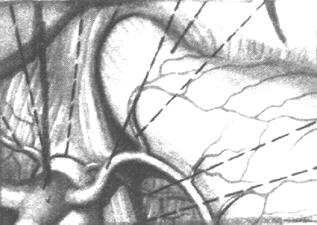

| Рис 1. Наружный мышечный слой

1. Брюшная часть пищевода

2. Кардиальная вырезка

3. Дно желудка

Итак началом этого участка Ж.К.Т. можно считать ту часть где пищевод соединяется с диафрагмой. В этом месте мышечная оболочка пищевода тесно сращена мышечной оболочкой диафрагмы образуя таким образом круговой мускул – “сфинктер”. В то - же время некоторые мышечные пучки диафрагмы присоединяются к стенке пищевода, и с ним идут ко входу в желудок. Круговые мышечные волокна пищевода располагаются в этом отделе иначе чем в верхних отделах и в свою очередь также принимают участие в формировании кругового мышечного жома. Это мышечное кольцо позволяет закрывать hiatus oesophagus и получило название "Сфинктер Губарева". Эти взаимоотношения пищевода и диафрагмы выполняют еще одну немаловажную функцию. Дело в том, что в зависимости от сокращения мускулатуры диафрагмы брюшная часть пищевода может изменяться в размерах. Кроме того и при вздутии желудка эта часть пищевода становится короче; при опущении желудка и в положении лежа брюшная часть пищевода удлиняется. Эта растяжимость объясняется различной подвижностью различных отделов желудка. Наименее подвижно место перехода пищевода в желудок. Эта часть расположена непосредственно под диафрагмой и фиксирована в ее отверстии. Помимо этого кардиальная часть желудка и его дно связаны с диафрагмой посредством lig. phrenicogastricum dextrum et sinistrum правая идущая от диафрагмы к передней поверхности пищевода и кардиальной части желудка, и левая идущая от диафрагмы к дну желудка. Правая входит в состав малого сальника, а левая входит в lig. gastrolienale которая и свою очередь переходит в большой сальник. После прохождения диафрагмы пищевод немного расширяется и делает крутой изгиб влево так что край перегиба образует на левой стороне просвета нечто вроде заслонки и препятствующей до определенной степени забрасыванию содержимого желудка в пищевод. Мышечная оболочка желудка как известно является продолжением мышечной оболочки пищевода. Наружные (продольные) волокна пищевода в области cardia, расходятся в различных направлениях, не достигая однако большой кривизны. Большая часть этих волокон переходит на малую кривизну.